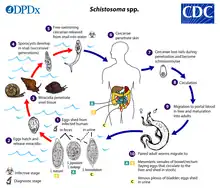

Transmission and life cycle

Infected Schistosoma individuals release eggs into water via their fecal material or urine. A collection of stool samples under a microscope will show the eggs of S. intercalatum, S. mansori, and S. japonicum. Looking at a urine sample under a microscope would reveal the eggs of S. haematobium and rarely, the eggs of S. mansori.[38] After larvae hatch from these eggs, the larvae infect a very specific type of freshwater snail. For example, in S. haematobium and S. intercalatum it is snails of the genus Bulinus, in S. mansoni it is Biomphalaria, and in S. japonicum it is Oncomelania.[39] The schistosome larvae undergo the next phase of their lifecycles in these snails, spending their time reproducing and developing. Once this step has been completed, the parasite leaves the snail and enters the water column. The parasite can live in the water for only 48 hours without a mammalian host. Once a host has been found, the worm enters its blood vessels. For several weeks, the worm remains in the vessels, continuing its development into its adult phase. When maturity is reached, mating occurs and eggs are produced. Eggs enter the bladder/intestine and are excreted through urine and feces and the process repeats. If the eggs do not get excreted, they can become engrained in the body tissues and cause a variety of problems such as immune reactions and organ damage.[12] While transmission typically occurs only in countries where the freshwater snails are native, a case in Germany was reported where a man got schistosomiasis from an infected snail in his aquarium.[40]

Humans encounter larvae of the schistosome parasite when they enter contaminated water while bathing, playing, swimming, washing, fishing, or walking through the water.[41][42][38]

Life cycle

The life cycle stages:[43]

- The excretion of schistosome eggs in urine or feces depending on species

- The hatching of the eggs leading to release of the free-swimming, ciliated larvae called miracidia

- Miracidia find and penetrate the snails, which are the intermediate hosts (specific species of snails is dependent on the species of schistosoma)

- Within the snails, two successive generations of sporocysts occur

- Sporocysts give rise to the infective free-swimming larvae with forked tails called cercariae, and they leave the snails to enter the water

- Cercariae find the human hosts and penetrate their skin

- Upon entrance into the human hosts, cercariae lose their tails and become schistosomulae

- The schistosomulae travel to the lungs and heart via the venous circulation

- They migrate to the portal venous system of the liver where they mature into the adult form with two separate sexes

- The adult male and female are paired together, exit the liver via portal venous system, and travel to the venous systems of the intestines or bladder (species dependent) and produce eggs

- S. japonicum - superior mesenteric veins (but can also inhabit inferior mesenteric veins)

- S. mansoni - inferior mesenteric veins (but can also inhabit superior mesenteric veins)

- S. haematobium - vesicular and pelvic venous plexus of the bladder (occasionally rectal venules)

- S. intercalatum and S. guineensis - inferior mesenteric plexus (lower portion of the bowels compared to S. mansoni)

Schistosomes can live an average of 3–5 years, and the eggs can survive for more than 30 years after infection.[19]